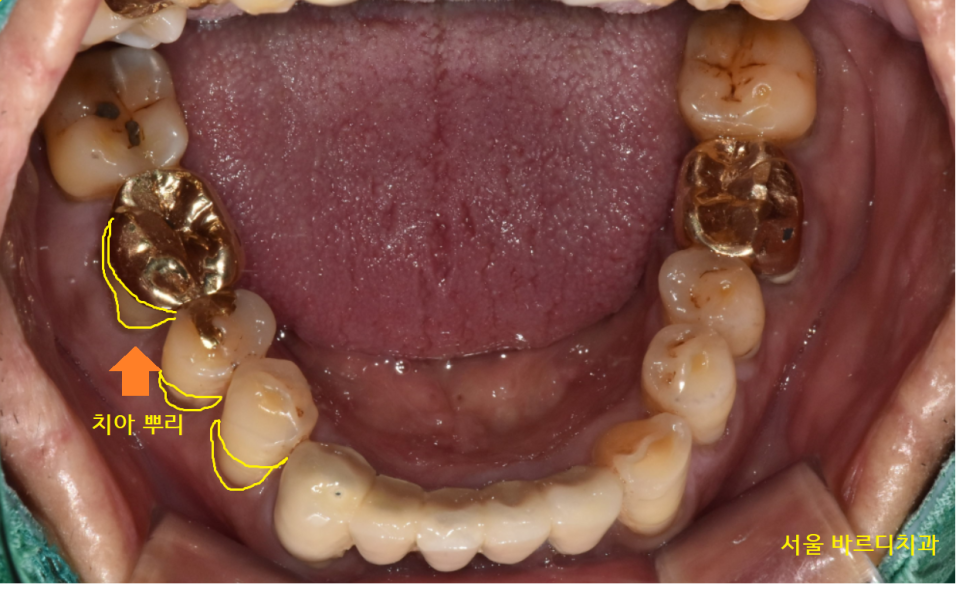

불편함을 호소하신 오른쪽 아래

잇몸뼈가 많이 내려가

치아 뿌리가 노출된 상황이었습니다.

23.04.24